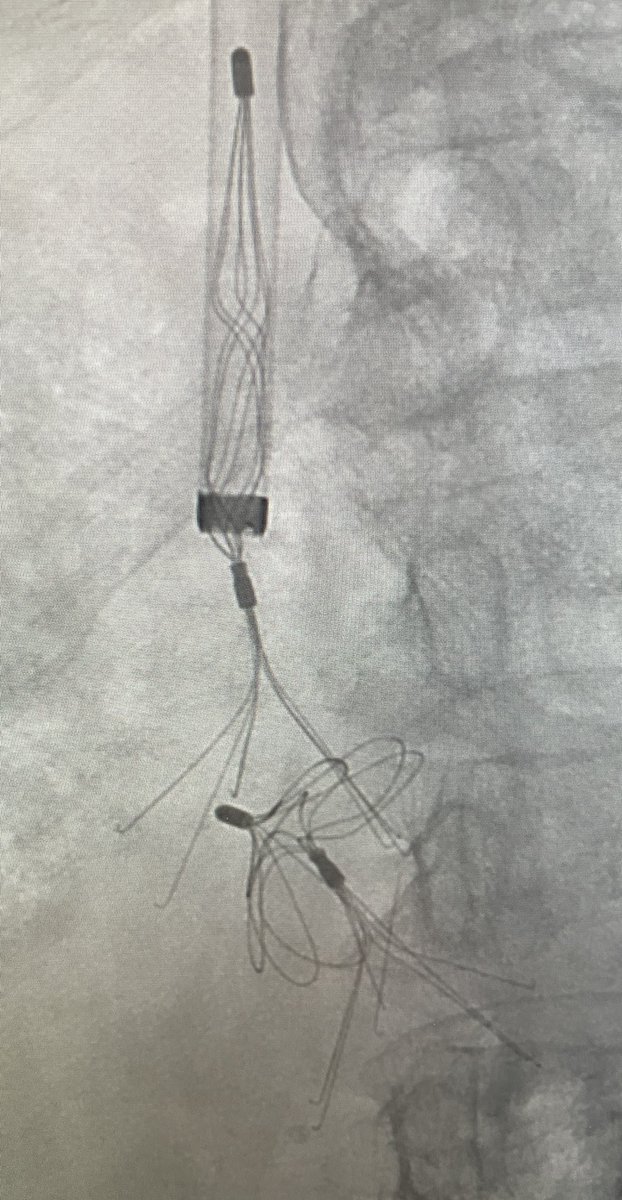

Don't step on this coiled rattler. Large gastroesophageal varices can be fragile and bleed quickly! Antegrade coil and plug embolized-- does that make it a CATO/PATO? #irad @IrColorado